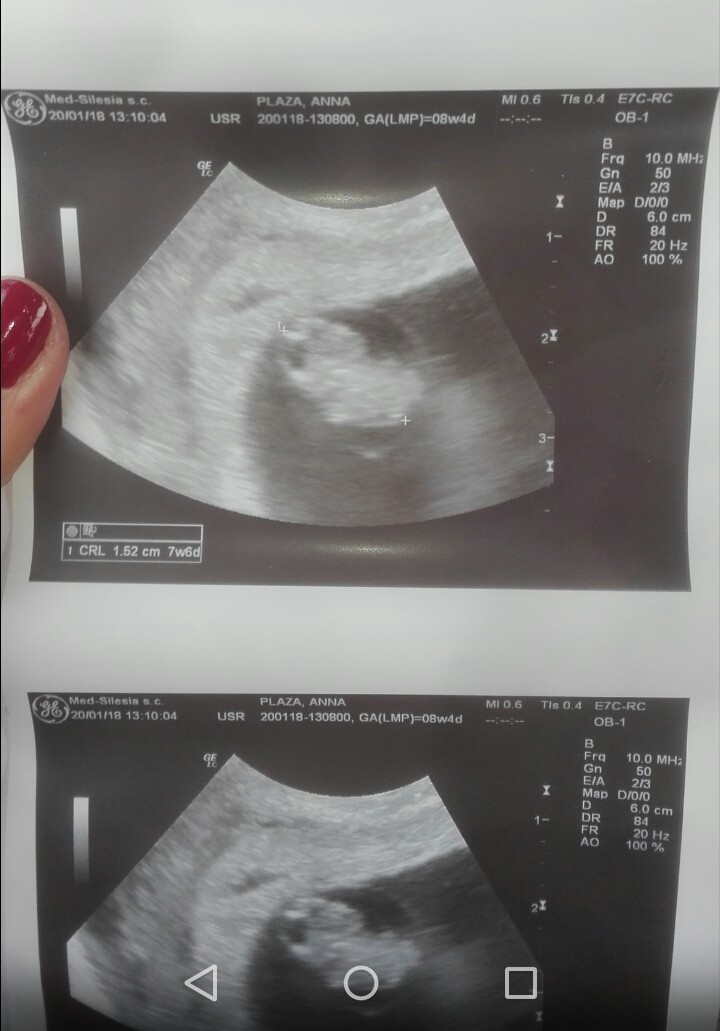

Aaaaaa popłakałam się ze szczęścia <3 groszek pomachał mi rączkami, widziałam i słyszałam serduszko, 158 uderzeń na minutęjest cudnie!Zobacz załącznik 836080 Zobacz załącznik 836081